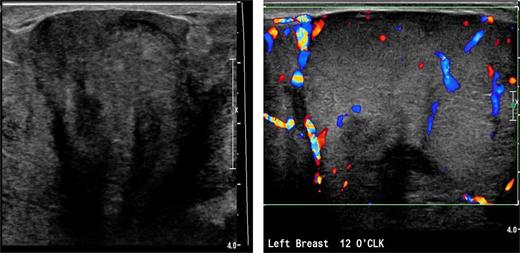

Due to pain and size of the right breast mass, the patient was unable to have mammography. Bilateral breast and axillary ultrasonography was performed. This showed a large heterogeneous solid mass with internal vascularity replacing all normal expected left breast tissue (Fig. 2). The size was difficult to be accurately defined on ultrasonography due to its large size. In the left axilla, a 1.8-cm nonspecific lymph node was identified with slightly prominent cortices. There were no suspicious findings in the right breast or right axilla. The patient had core biopsies of the left breast and left axillary node. Initial histopathological analysis suggested a fascicular pseudoangiomatous stromal hyperplasia or phyllodes tumor. The left axillary lymph node biopsy revealed chronic lymphadenitis without neoplastic cells. Further workup with a chest and abdomen computed tomography (CT) scan was performed, which showed no evidence of metastatic lesion.

Left breast ultrasound demonstrates a heterogeneous solid mass with internal vascularity replacing the normal breast tissue.